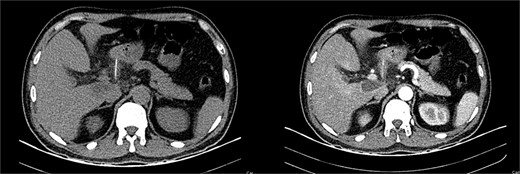

It unveiled a linear hyperdensity behind a thickened stomach wall in the lesser sac, in close contact with the pancreas and duodenum; it had areas of surrounding fat stranding and tissue thickening without pneumoperitoneum. A perforation caused by a fishbone was suspected (Figs 1 and 2).

(A) CT, the fishbone is seen in the lesser sac. (B) Contrast enhanced CT, the fishbone is seen free in the lesser sac in close contact to the pancreas.